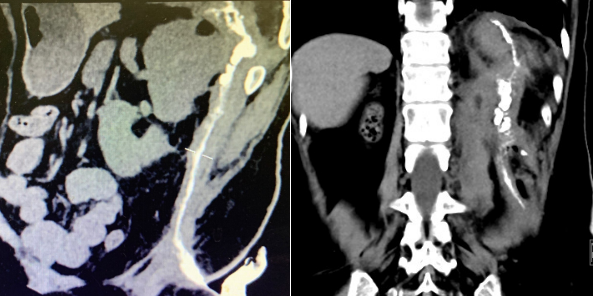

术后窦道形成病人,CPR、冠状位显示窦道的全程走行现状及与临近组织脏器的解剖关系